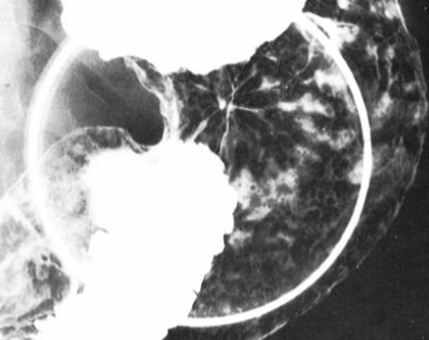

Varice esofagiene